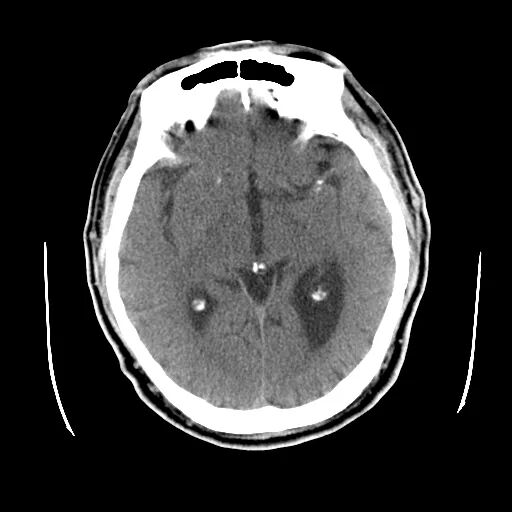

术前影像

颅脑CT:颅内多发腔隙性梗塞灶。